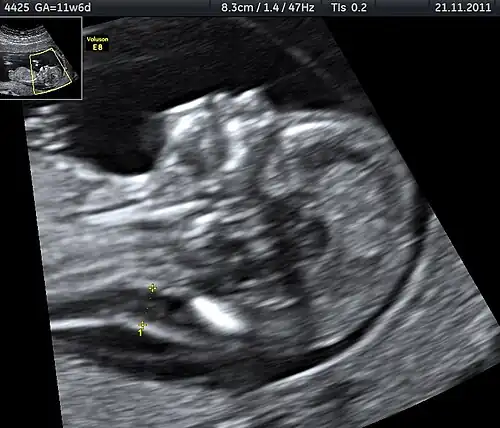

Ultrasound

Prenatal ultrasound can be used to screen for Down syndrome. Findings that indicate increased chances when seen at 14 to 24 weeks of gestation include a small or no nasal bone, large ventricles, nuchal fold thickness, and an abnormal right subclavian artery, among others.[113] The presence or absence of many markers is more accurate.[113] Increased fetal nuchal translucency (NT) indicates an increased possibility of Down syndrome picking up 75–80% of cases and being falsely positive in 6%.[114]

Ultrasound of fetus with Down syndrome showing a large bladder